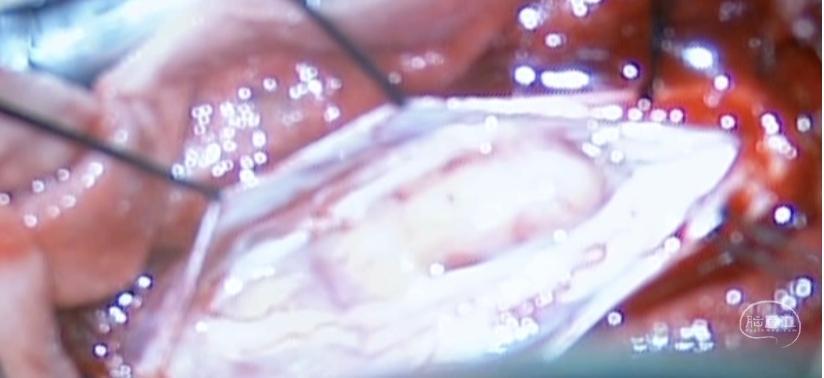

图4.切除肿瘤基地,硬膜重建

图4.切除肿瘤基地,硬膜重建

图5.肿瘤完整切除,脊髓无副损伤

图6.肿瘤完整全切除

图6.肿瘤完整全切除

椎管内神经鞘瘤显微切除,分块和整块切除需依据肿瘤大小,部位,形态,血供,与脊髓,神经根及椎间孔等结构累及关系。肿瘤切除时仔细辨明肿瘤起源,神经根,脊髓界面,松解黏连蛛网膜,0牵拉脊髓和肿瘤原位切除交替进行。双极电凝强度及吸引器使用时刻要注意器械副损伤对脊髓功能影响,最大程度对保护和恢复脊髓神经功能。

本例手术肿瘤切除及硬脊膜缝合用时25分钟,减少脊髓暴露时间和降低感染发生。载瘤神经的处理根据肿瘤与神经是否粘连,行神经切除或保留或梳理粘连带。术后硬脊膜严密缝合,避免脑脊液漏发生。本例考虑到存在多种脊柱不稳定因素存在,因此采用全椎板切除和椎弓根钉棒内固定术恢复脊柱稳定性。